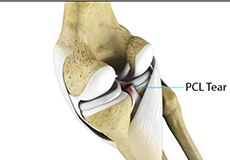

PCL Injuries

Posterior cruciate ligament (PCL), one of the four major ligaments of the knee, is situated at the back of the knee. It connects the thighbone (femur) to the shinbone (tibia). The PCL limits the backward motion of the shinbone.